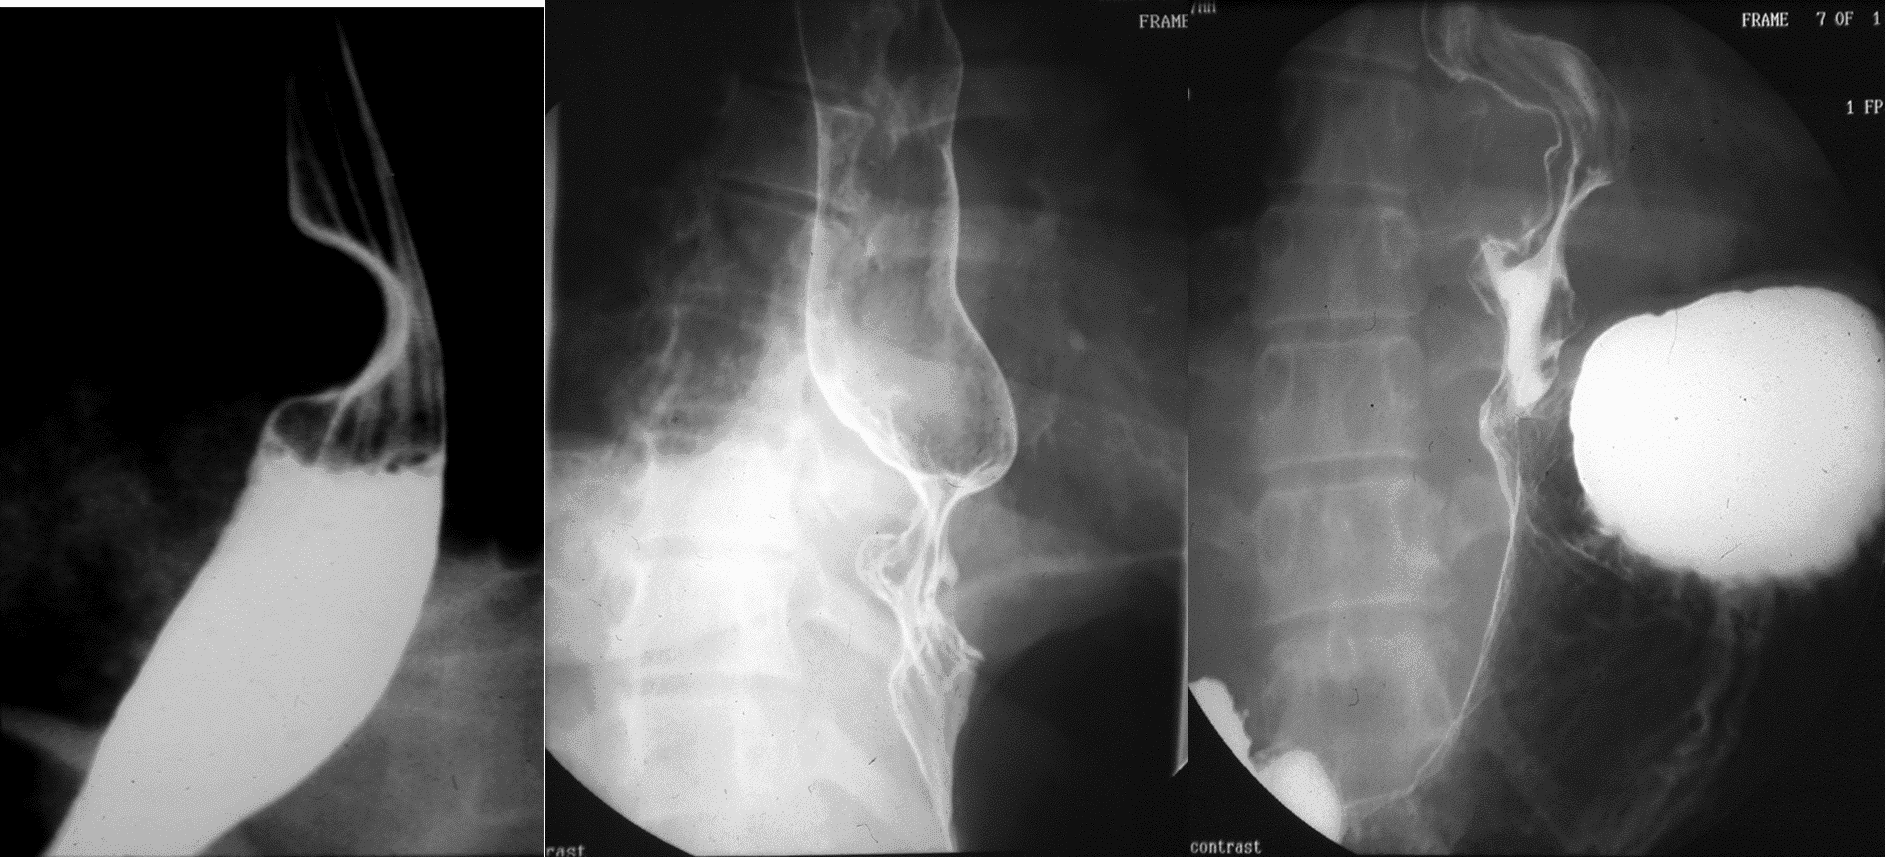

Езофагографія з барієвим контрастуванням може показати внутрішньопросвітне звуження від компресійного ефекту утворення, з плавно підвищеним дефектом наповнення, що виступає від просвіту і окреслює розмір пухлини (зобр. 2).[3,7]

Зображення 2. Езофагографія з барієвим контрастуванням, що демонструє внутрішньопросвітне звуження від компресійного ефекту утворення з підвищеним дефектом наповнення, що виступає від просвіту та окреслює розміри пухлини.